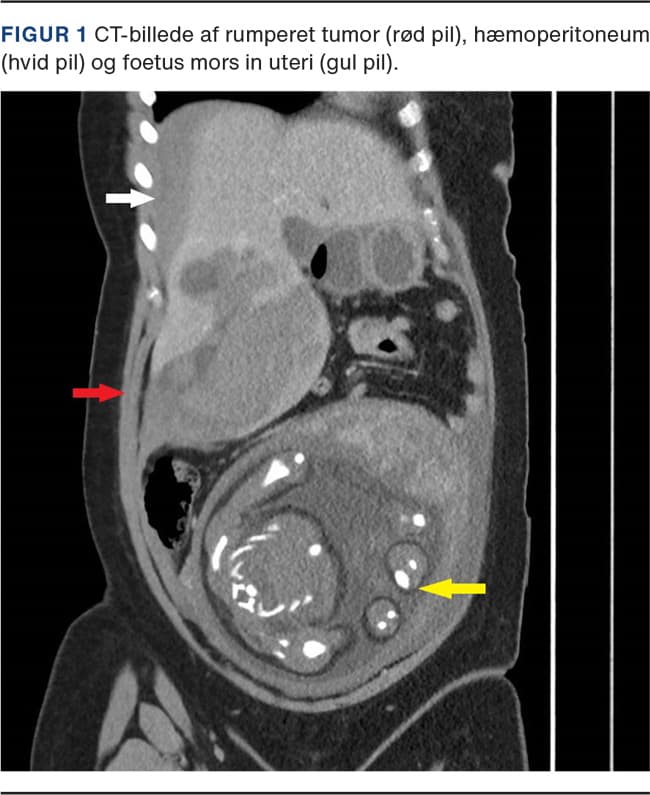

Ved den akutte vurdering var differentialdiagnoserne præeklampsi, HELLP, galdestensanfald, pankreatitis, lungeemboli samt akut myokardieinfarkt som alle blev udelukket pga. normal paraklinik, ekg og A-gas-analyse. Der fandtes initialt let hypotension 95/62 mmHg og en puls på 82 slag/min. Door-step-kardiotokografi (CTG) fandtes normal og reaktiv. Pga. vedvarende smerter blev hun indlagt til observation. En kontrol-CTG viste intrauterin fosterdød, hvorefter patienten kort efter blev akut dårlig, med voldsomme smerter i epigastriet strækkende sig under højre kurvatur og klinisk tegn på hypovolæmisk shock. Der fandtes umiddelbart ikke kliniske tegn til placentaløsning (abruptio), idet uterus blev vurderet blød og uøm, og der ikke var observeret nogen vaginal blødning. Pga. mistanke om intraabdominal blødning udførtes akut CT, der viste blødning fra en rumperet leverforandring (Figur 1).